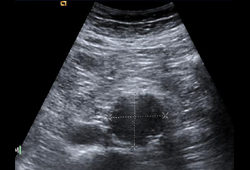

- მუცლის ღრუს ულტრაბგერითი გამოკვლევა